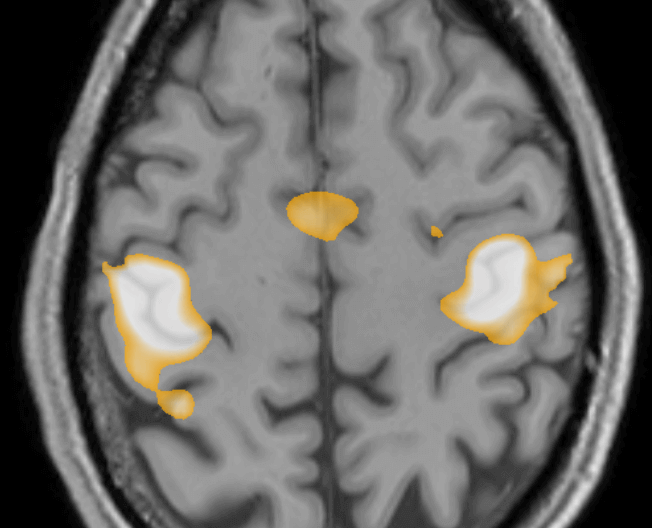

Speech, and in particular the word-generation task, localizes to Broca’s area. This is most commonly found on the left, but rarely (as in the unusual example below) can be bilateral with a large component on the right. The right-sided dominance of speech in this right-handed patient was confirmed with WADA testing.

fMRI activity with word generation - unusual case of right-sided dominant speech

Right-sided speech dominance on fMRI